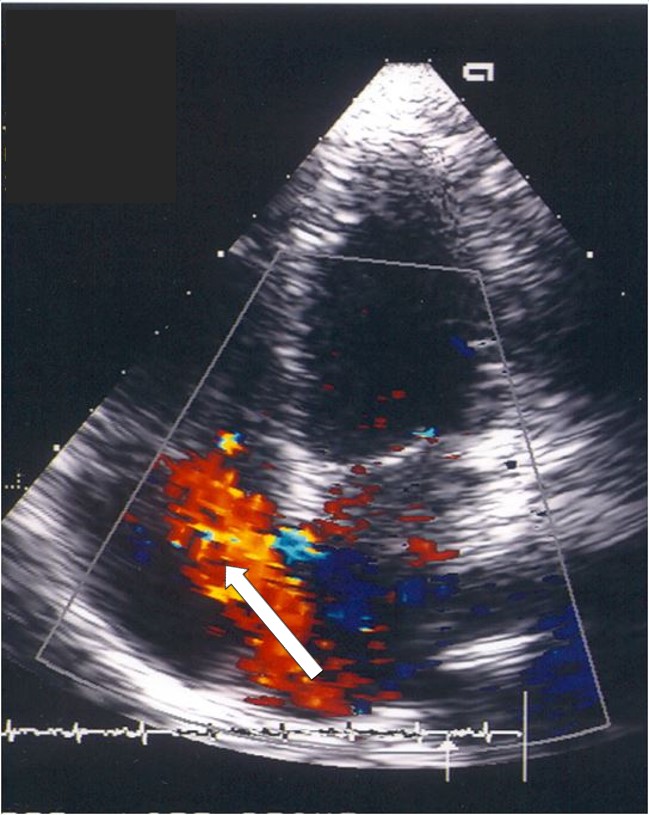

Leaking valve

• Secondary to systemic illnesses (e.g. rheumatoid arthritis, syphilis).These valves are either unable to close (regurgitation), open normally (stenosis), or a combination of both.